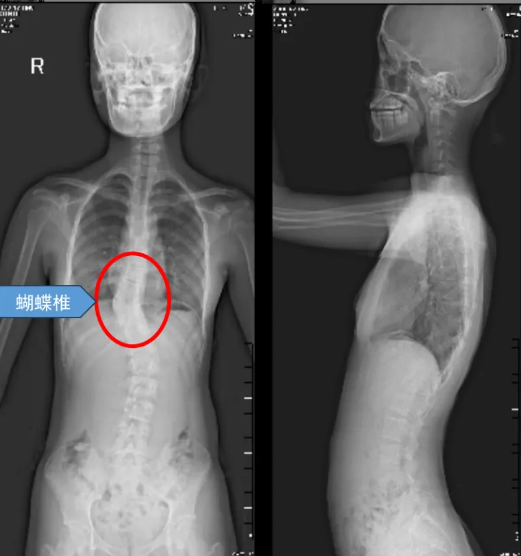

蝴蝶椎,这美丽的名字背后,却隐藏着无尽的痛苦与挑战。蝴蝶椎畸形,作为一种罕见的先天性脊柱畸形,也被称为矢状椎体裂,其发病原因是胚胎发育期间脊柱椎体的两个软骨中心在发育过程中未能正常融合,导致椎体成为左右对称的两个三角形骨块,形似蝴蝶的双翼,故得名蝴蝶椎。蝴蝶椎畸形并不一定需要手术,但在某些情况下,如多发蝴蝶椎或蝴蝶椎发育高度不平衡时,可能导致脊柱侧凸、后凸等脊柱畸形及疼痛、活动能力下降、心肺功能障碍等,就需要尽早手术干预了。

家在遂溪的13岁女孩小亭,患的就是这样一种疾病。而且由于该蝴蝶椎前后发育不平衡,导致小婷脊柱明显畸形,长期遭受着侧弯和驼背的折磨,不仅身体形态不美观,而且运动能力也大幅下降,跑几步就气喘吁吁,心理上更是承受着巨大的压力。家人焦急万分,四处打听,方才得知小亭这种病需要做手术,但是该手术难度高,风险大,不禁又犯了难,到底该不该做手术?要到哪里做?